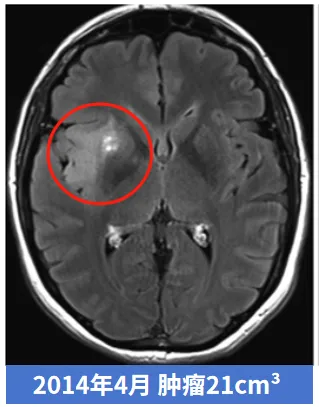

良性胶质瘤可恶化升级为恶性

这是一位40多岁女性,偶然诊断出低级别胶质瘤,医生建议保守观察,此时肿瘤仅3cm³。然而,肿瘤一直不断增长,6年后,肿瘤以肉眼可见的速度进一步增大,很麻烦了,已经11cm³……更让人想不到的是这个肿瘤从11cm³发展到21cm³,仅仅用了5个月!很遗憾,肿瘤不仅长大,术后的病理显示甚至已经恶化成,中位生存期仅14.6个月的4级胶质母细胞瘤。

▼肿瘤发展进程变化图片

该则案例来源于INC国际Rutka教授主编的知名神经外科期刊JNS真实案例,原本预后较佳的低级别胶质瘤,错过了最佳手术时期,最终竟恶化成级别最高的胶质母细胞瘤,患者后悔不已,这时就算再手术,也不能明显延长生存期。

本病例显示,无症状低级别胶质瘤的进展也不一定都是匀速的,也可能不经过WHO 3级胶质瘤的过度,就急性发展为胶质母细胞瘤。